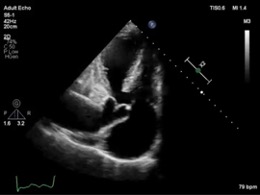

Əməliyyat olunmamış 52 yaşlı Truncus arteriosus tip4 xəstə Dərc edilib: Cild 23, Nömrə 1, 2023 / Nəşr tarixi: 14.10.2023 Ləman Eyvazlı, Oqtay Musayev, Firdovsi İbrahimov